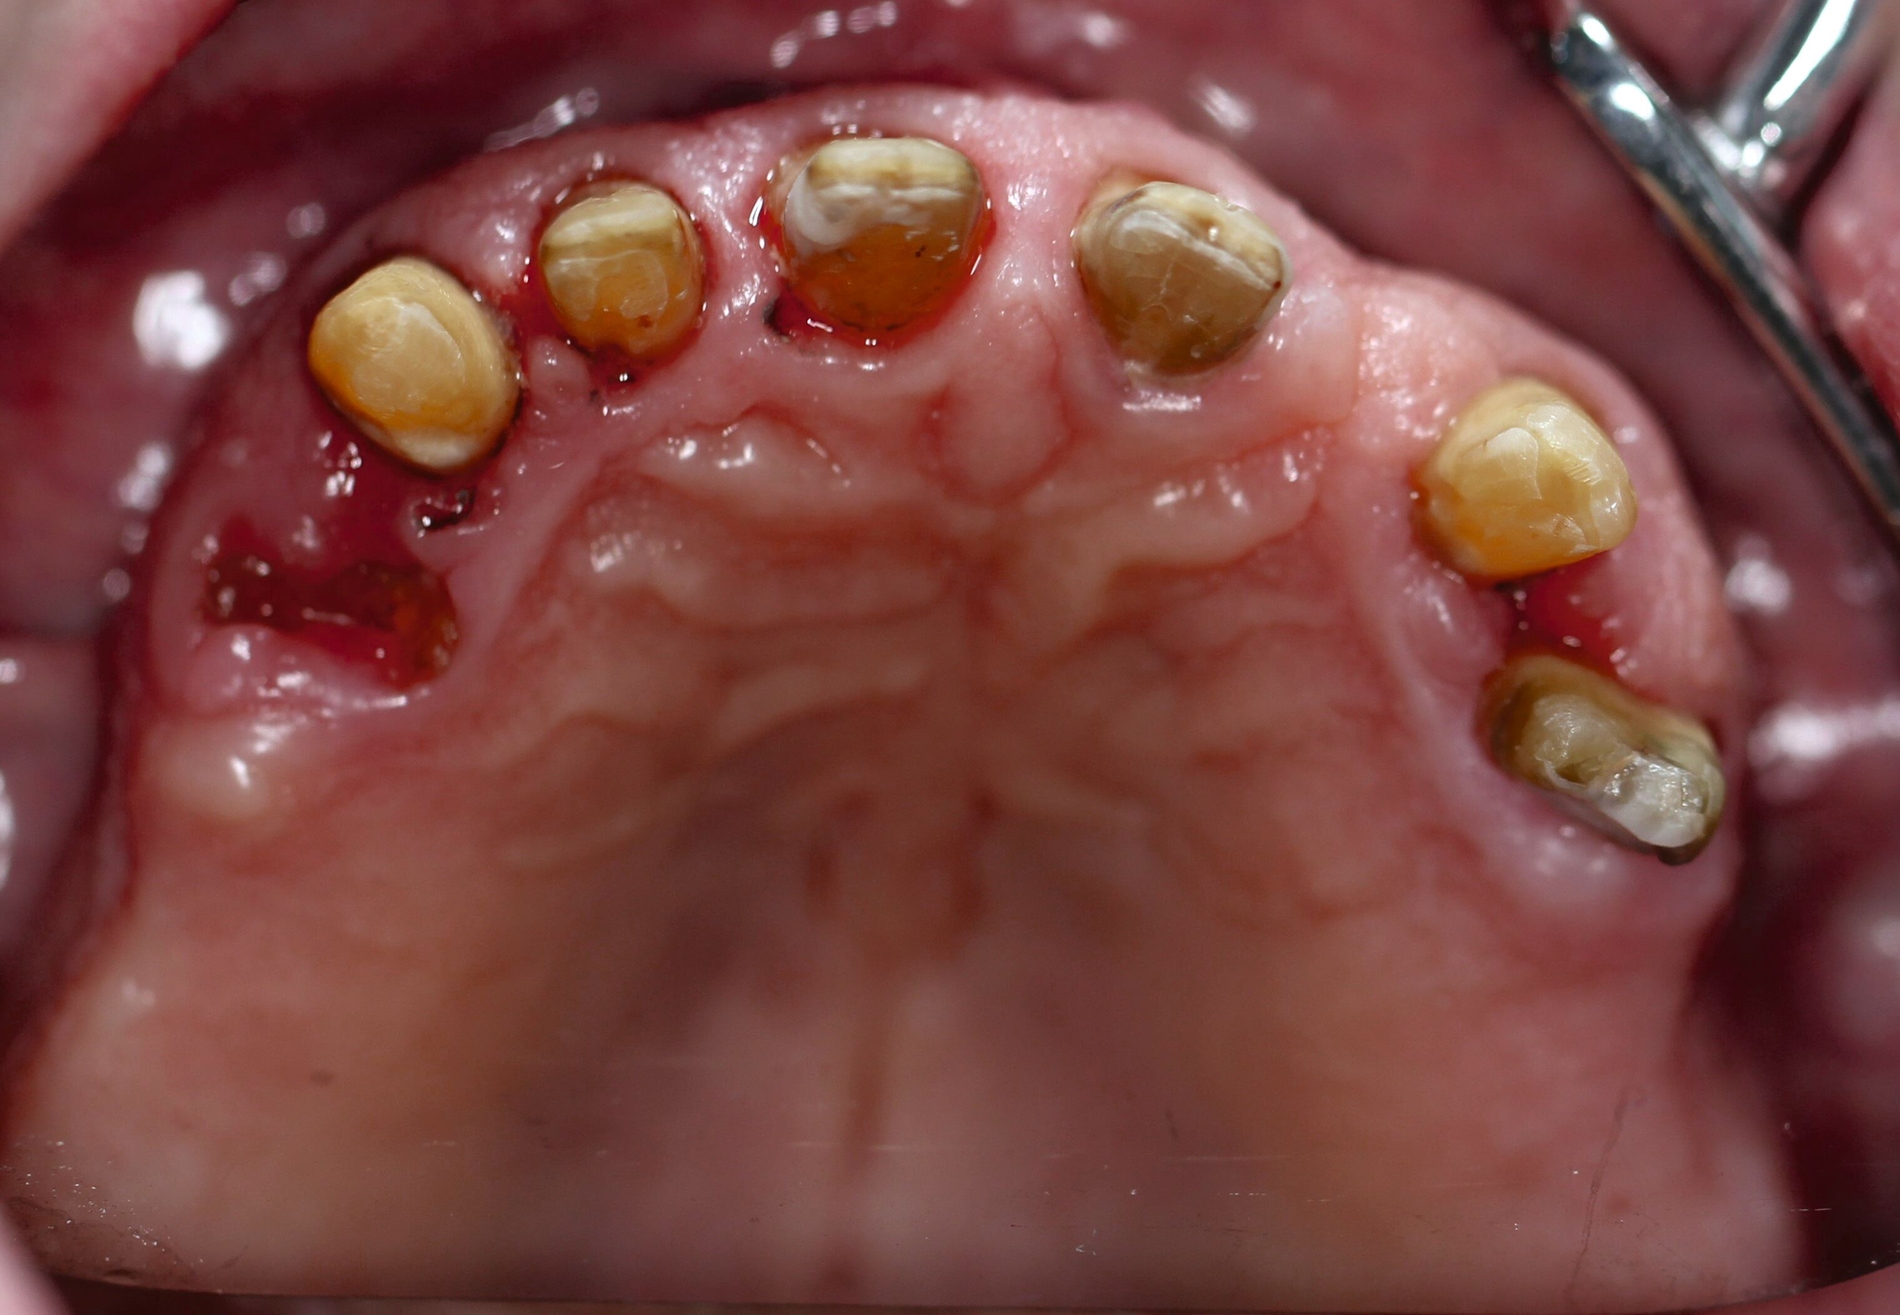

Der Patient stand unter der Dauermedikation von Metformin 500 mg, Ramipril 5 mg, Torasemid 10 mg, Metohexal 47,5 mg, Simvastatin 20 mg, Tamsulosin 0,4 mg und 3 mg Marcumar (INR 2,5–2,8) bei Zustand nach einer Bypass-Operation im Jahr 2019. Klinisch zeigten sich im Oberkiefer insuffiziente, verblockte und verblendete NEM-Kronen mit beidseitigen Gold-Extensionen distal, die über Geschiebe mit dem anterioren Anteil verschraubt waren (Abbildungen 1 und 2). Der Patient berichtete, dass die vorhandenen Kronen und Brücken 1984 eingesetzt worden seien.

Besonders auffällig war eine Dezementierung, die klinisch durch rechtsseitigen Druck und Zug mit einer Pinzette und daraufhin austretende Sulkusflüssigkeit in Regio 14 detektiert wurde. Da entsprechend des synoptischen Behandlungskonzepts [Naumann et al., 2010] bei prothetischer Neuversorgung eine gesamte Evaluation der Restpfeiler erfolgen muss, wurden zunächst die Kronen im Oberkiefer durch Schlitzen und Aufbiegen entfernt. Erst danach ließ sich deren Erhaltungswürdigkeit abschließend beurteilen.